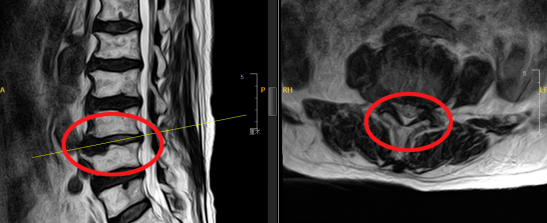

脊柱外科副主任医师张冶接诊后,经过详细地问诊、触诊,并结合影像学检查,诊断李奶奶为重度腰椎间盘突出并伴腰椎椎管狭窄。因腰脊神经受到严重的压迫,这才引起了一系列的腰、腿疼痛。

考虑老人基础疾病多,身体状况相对较差一些,如采用保守治疗,卧床时间长,引发并发症的几率较大;如采用传统手术治疗,老人在创伤、麻醉耐受程度等方面也会存在较大风险,且恢复时间长,也需要长时间卧床修养。脊柱外科尚军主任、张冶医生带领医疗小组制定手术方案,决定在脊柱内镜下进行腰椎间盘摘除、椎管减压术,为李奶奶解除顽“脊”。